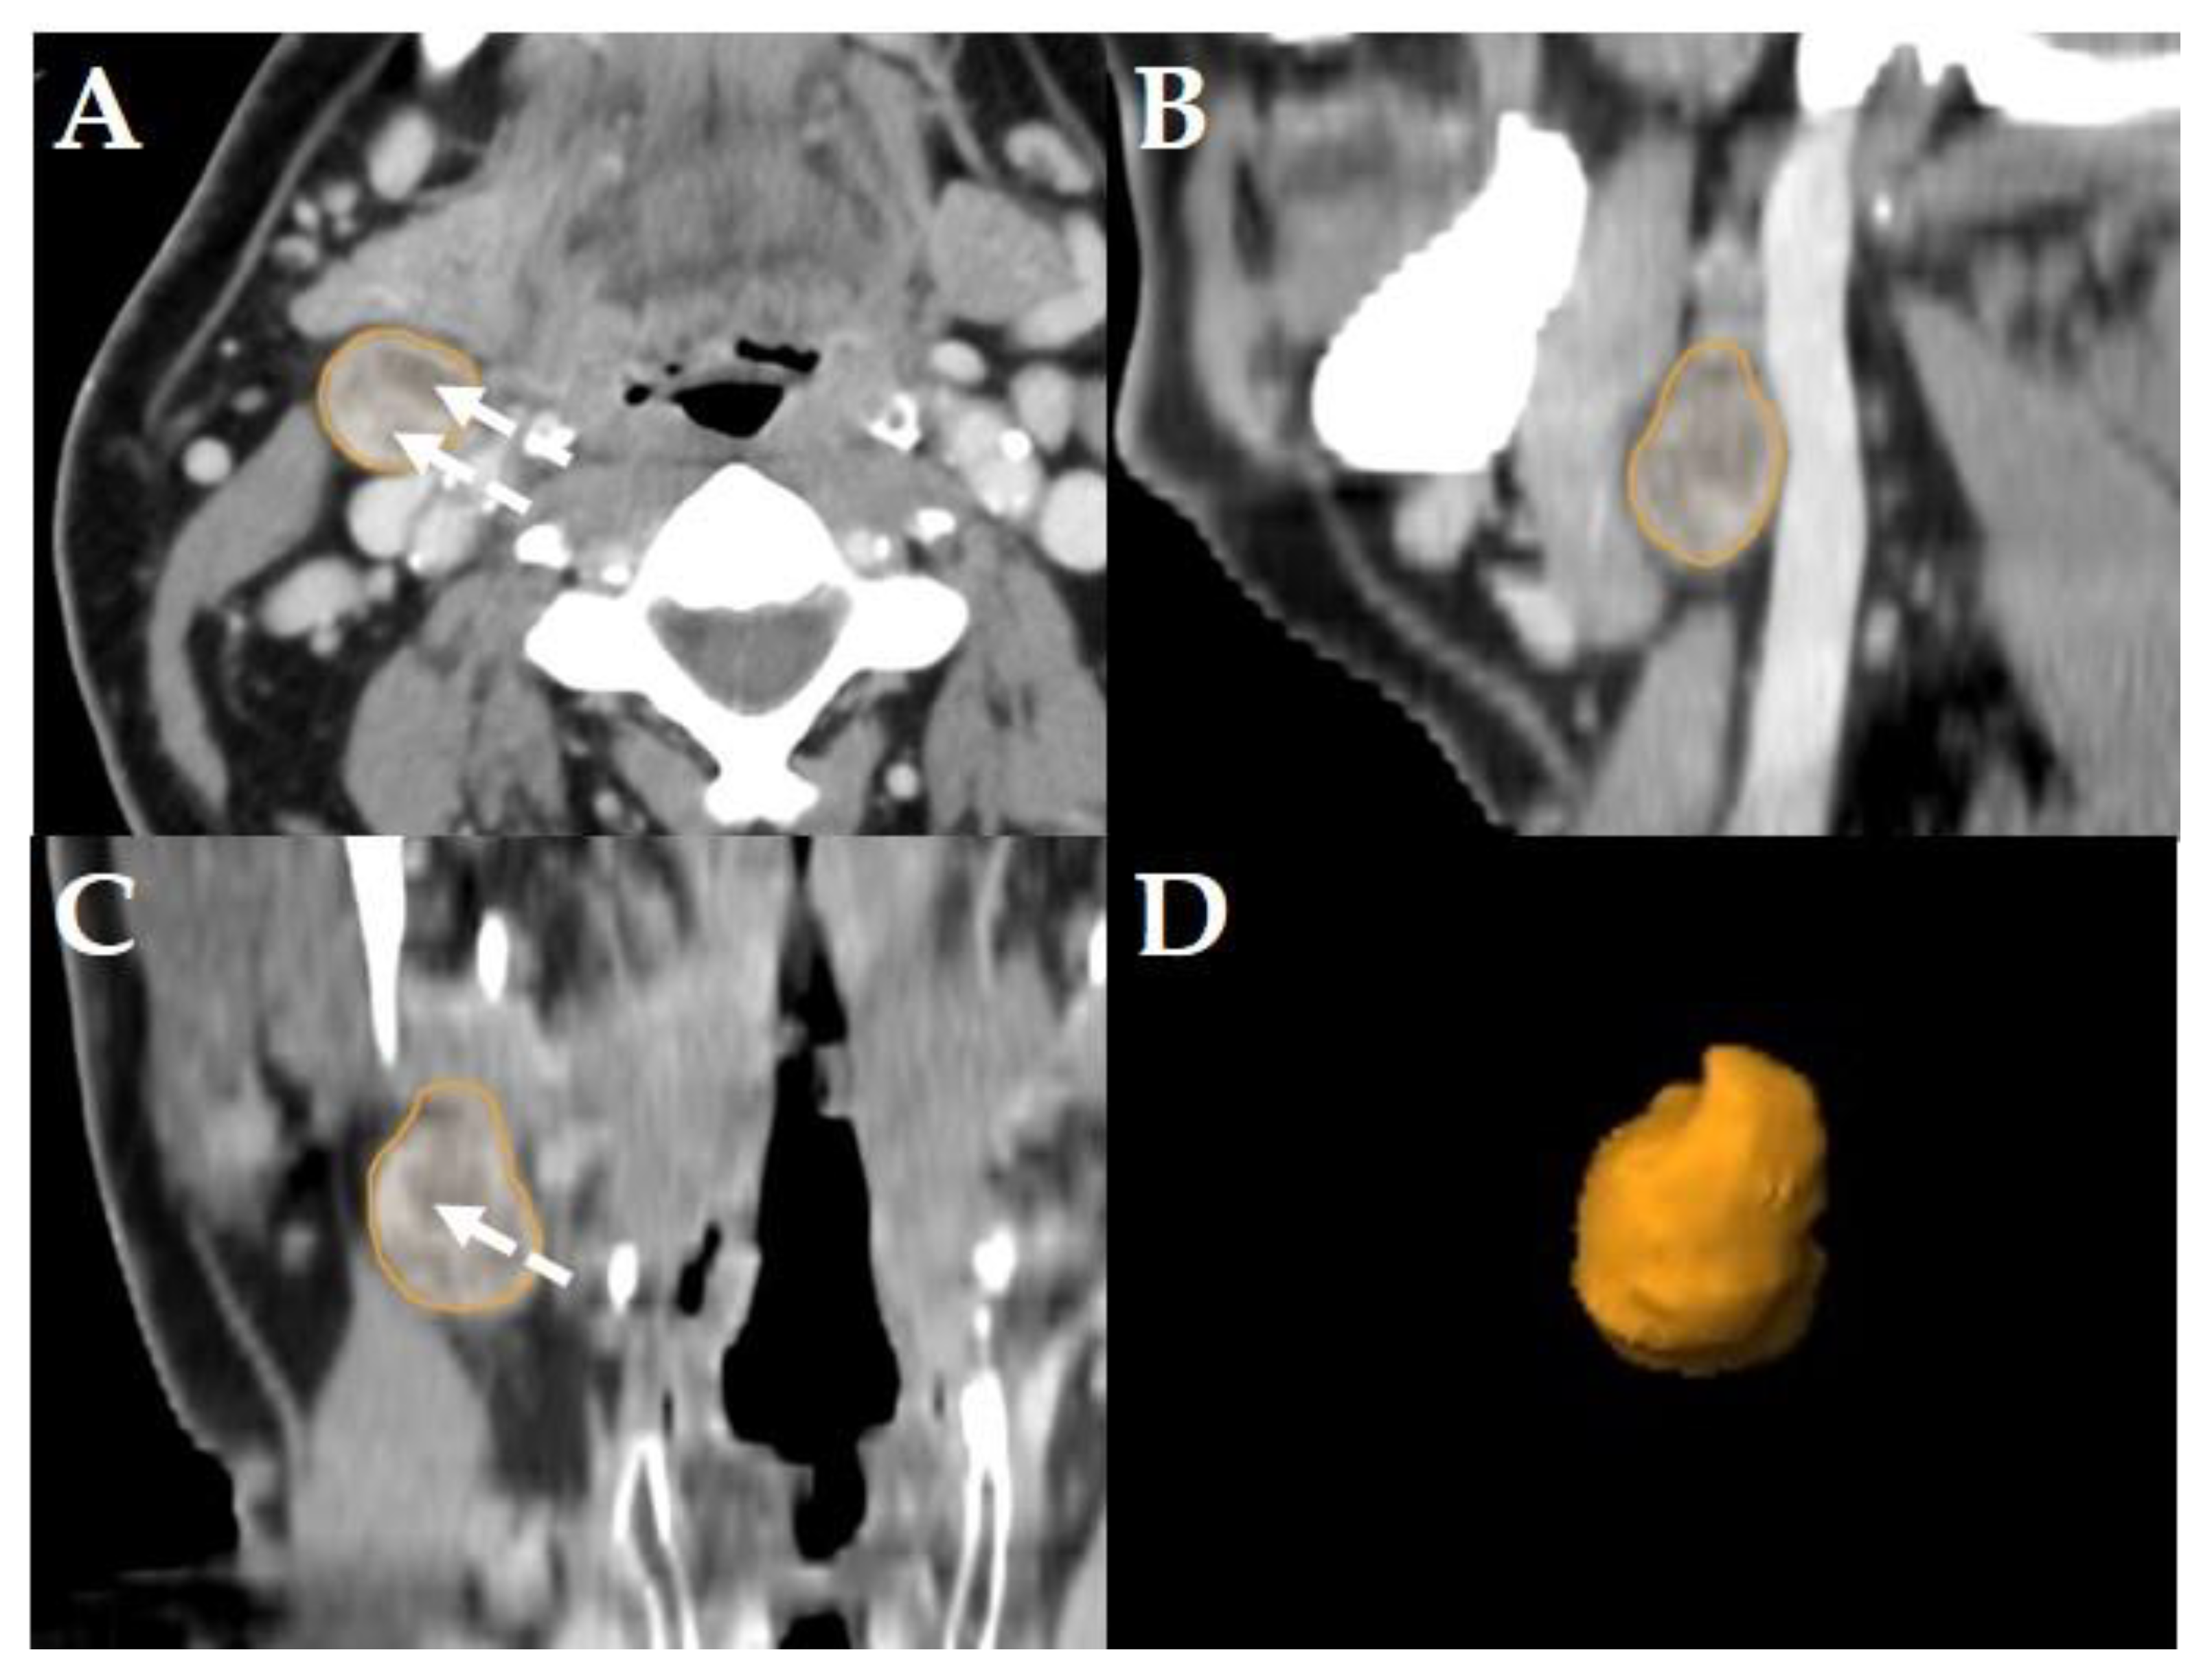

Figure 3. Example of a LN classified as “pathologic with ECS” in a Staging-CT of a 53-year-old, male HNSCC-patient of the oral cavity staged cT2 cN3b cM0. Manual segmentation in the axial plane (A); sagittal (B), coronal (C) reformatted views and three-dimensional rendering (D) of the LN are provided by the software. Solid arrows show soft tissue infiltration and an irregular LN capsule. Dashed arrows show central necrosis.

LNs were classified “pathologic with ECS” if in staging-, planning- or restaging-CTs, in addition to the criteria mentioned above [5,6], apparent fat/soft-tissue infiltration, infiltration of the sternocleidomastoid muscle, the internal jugular vein, or the carotid artery was observed [7]. Consequently, all LNs classified as “pathologic with ECS” were considered “pathologic”, too, but not all “pathologic” LNs were classified “pathologic with ECS” (Figure 3).

Consequently, the classification of the segmented LNs in “pathologic” (Figure 2), “pathologic with ECS” (Figure 3) and “non-pathologic” (Figure 4) by the two experienced head-and-neck-radiologists based on established criteria [5,6,7] was defined as reference.